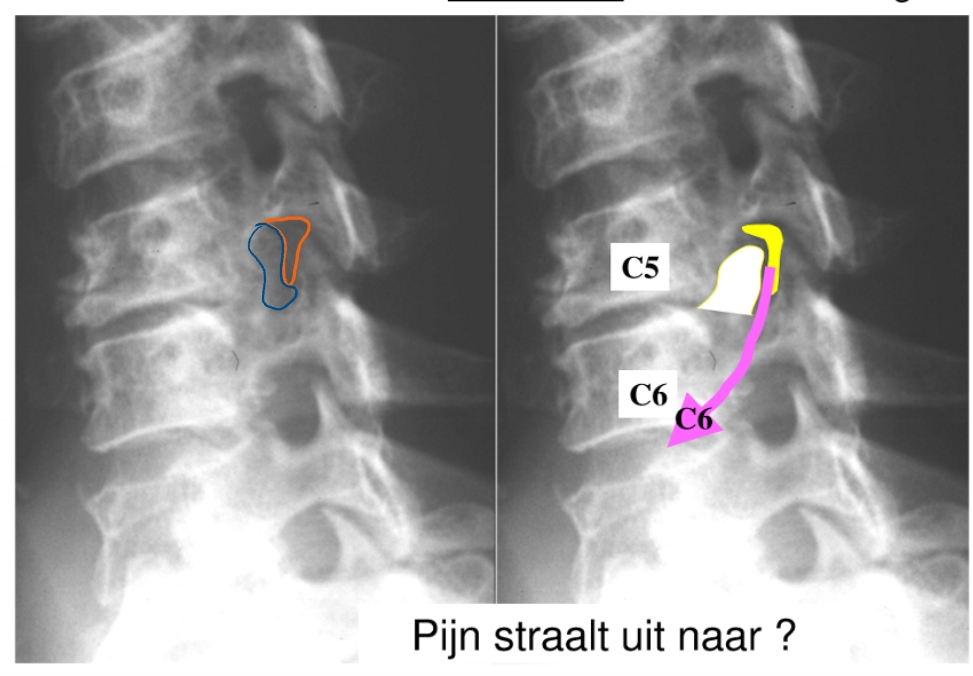

spinale zenuw → gaat richting duim

= uncartrose C5-C6 (links)

klachten: cervico-brachialgie

blauwe gedeelte = osteofiet → vernauwing van foramen intervertebrale door verbening

zenuw heeft bijna geen plaats meer en wordt gekneld → last vanuit nek straalt uit naar duim

dermatoom